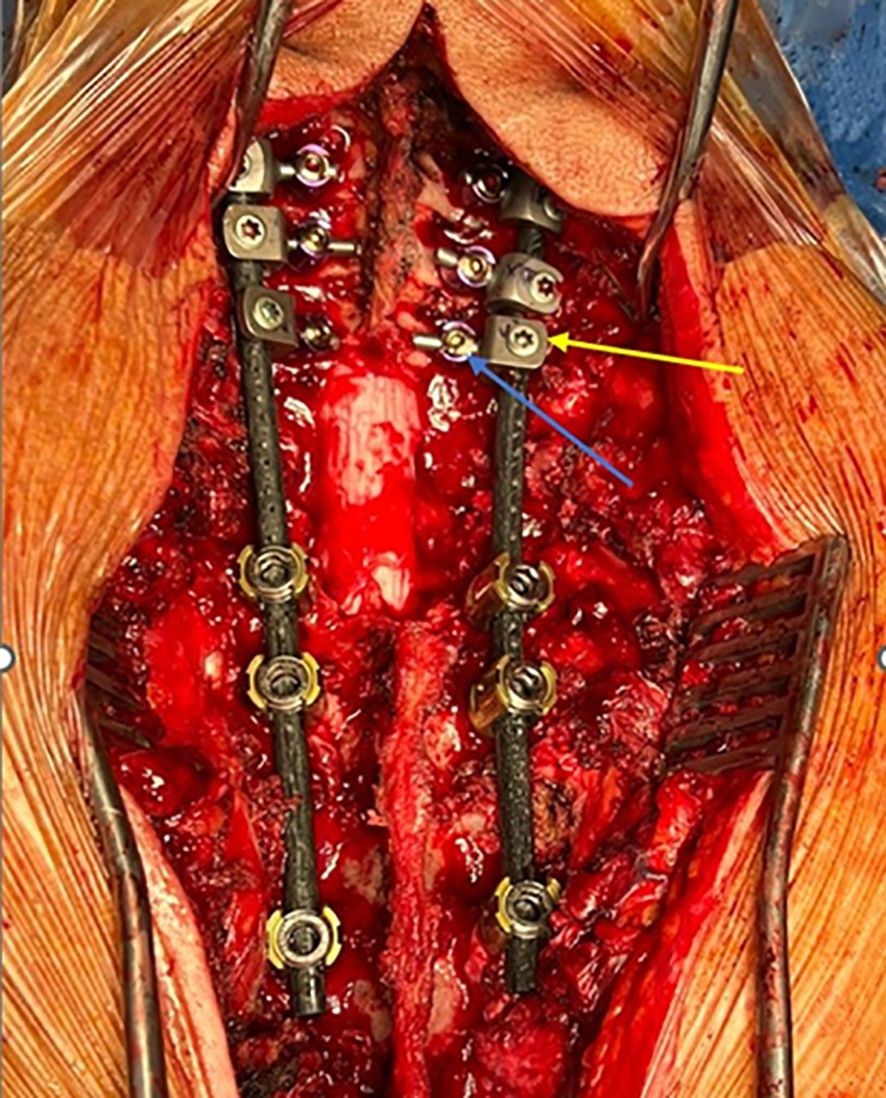

A hybrid system of carbon fiber rods, custom-made titanium connectors and cervical screws was used in the cervical and cervico-thoracic spine. CF-PEEK or LCFRP rods were used to bridge the cervical and thoracic spinal instrumentation. In cases where LCFRP rods were utilized, 5.5 mm titanium implants were placed in the thoracic spine, while in cases where CF-PEEK implants were utilized, 5.5 mm CF-PEEK screws were used instead. A customized titanium connector was used to connect the cervical/occipital fixation to the carbon rod. This customized titanium connector consists of a tulip for connection to the carbon fiber rod, and a stem for connection to the cervical/occipital fixation (Figures 1, 2). The connector stem could be bent and then cut or shortened as needed once the construct was secured (Figures 3, 4). The connections between the custom titanium connectors and the carbon fiber rods/standard screw tulips were secured using locking screws. The interface between the carbon fiber rod and the tulip of the custom titanium connector is illustrated by Figure 2, where the rod was press-fit into the connector tulip and retained in place by friction and interference. During final implantation, locking screws were also inserted into the tulips to further secure the connection between the tulips and the carbon fiber rods (Figure 3). A surgical drain was inserted, after which standard closure in layers was performed.

Figure 3. Clinical image of surgical construct. Custom connector is labelled in yellow; cervical lateral mass screw is labelled in blue.

This may also be in part due to the fact that we have sought to optimize the intraoperative placement of the screws, connectors, and rods. In the thoracic spine, the titanium screws were placed caudal to the level of the tumor to minimize interference of the implants with radiotherapy and imaging. In the cervical spine, lateral mass screws and the custom titanium connectors were placed cranial to the level of the pathology, and directed away from the tumor, so as to reduce potential implant interference. As far as possible, we have attempted to ensure that only the radiolucent carbon fiber rods remained at the level of the tumor (as illustrated by Figures 3 and 4), in order to facilitate postoperative imaging and radiotherapy delivery.